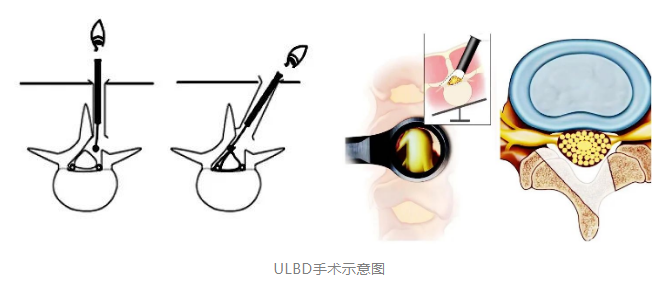

脊柱病医院院长郝定均及脊柱病医院腰椎病区主任刘团江查房后指出:患者腰椎管狭窄较重,双侧均有神经压症状,治疗需要完成双侧减压,才能达到治疗目的!传统的手术方式创伤较大、患者恢复时间更长。鉴于患者年龄轻,结合病史、体征、影像资料和查体表现等结果后制定单侧椎板入路双侧椎管减压手术(Unilateral laminotomy for Bilateral Decompression,ULBD)。

ULBD手术适用于双侧神经根受压需要手术的腰椎间盘突出症患者,采用“over-the-top”技术通过一侧入路实现双侧椎管的减压,实现椎管的扩大和神经减压,可以最大程度的保留了对侧的软组织和稳定结构,减少创伤。

“为了保证手术效果和安全性,我们在手术中特别引入了超声骨刀”杨俊松副主任医师介绍,“超声骨刀可根据不同组织的密度改变输出功率,对密度高的骨组织输出大功率以达到切骨的目的,但对周围硬膜及神经等伤害相对较小。杨俊松副主任医师积极完成相关检查后,当即为患者安排手术,确保患者早日缓解疼痛。